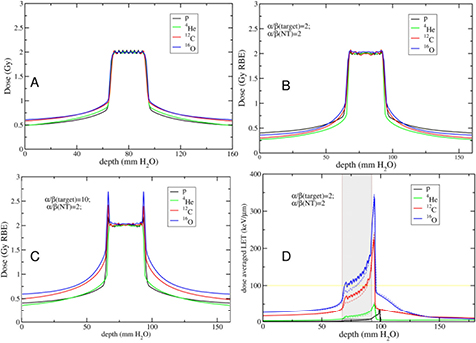

Both the longitudinal and lateral dose profiles (figure 4) resulting from the interaction of charged particles with the human tissues are important in CPT. The longitudinal profile is dominated by the inelastic electromagnetic interaction with atomic electrons, leading to a slow down of the primary particles. Lateral profile is mostly caused by the elastic scattering on target nuclei, and leads to a broadening of the beam. Nuclear interactions reduce the intensity of the primary beam and contribute to both longitudinal and lateral profiles.

Cell survival studies showed already many years ago (Blakely et al 1984) that heavy charged particles have an increased relative biological effectiveness (RBE) compared to x-rays, mostly described by an increase in the α parameter, resulting in steeper survival curves. The RBE is defined as the ratio Dx/Dp of the x-ray and particle radiation doses giving the same biological effective—e.g. 10% cell survival (RBE10). The RBE depends on several physical (LET6, dose, dose rate, fractionation, particle mass etc) and biological (intrinsic radiosensitivity, biological endpoint, oxygen concentration, cell cycle phase, proliferation rate, etc) parameters (Durante and Loeffler 2010). Data mining of RBE values (Friedrich et al 2013) from cellular experiments performed in the past 50 years with different ions always shows a large variance (figure 8). The general trend is always the same: an increase from low-LET up to 100–200 keV μm−1, and then a decrease at very high-LET caused by the overkilling effect. Light particles are generally more effective than heavy particles at the same LET, because they are slower and therefore have a narrow track width. The biological advantages of irradiating a tumor with a high-LET ion goes beyond the RBE for cell killing: the oxygen enhancement ratio (OER), cell-cycle variation in sensitivity, and sparing by fractionation are reduced with densely ionizing radiation, making CPT ideal against hypoxic tumors, or with many proliferating cells. More evidence is also accumulating showing that high-LET radiation has distinct radiobiological effects compared to low-LET, e.g. reducing angiogenesis and cell migration (Loeffler and Durante 2013). Taken together, these data suggest that using a charged particle with low-LET in the entrance channel (high velocity) but of relatively high-LET in the SOBP (low velocity) will provide a further biological improvement to the treatment beyond the physical advantages.

Standard image High-resolution imageProtons used in therapy generally have an entrance energy between 150 and 250 MeV (15–35 cm range in water), corresponding to a low-LET in water around 1 keV μm−1. The LET on the SOBP increases with depth in a range of 2–6 keV μm−1 (Paganetti 2014). It is expected that this modest LET increase will correspond to an increased RBE (figure 9), using the data from the same PIDE database shown in figure 8 (Tommasino and Durante 2015). However, the effect is arguably significant only in the last few mm of the SOBP. Thus, the proton therapy community has adopted a constant RBE of 1.1, which seems to be reasonable considering the unavoidable spread associated to RBE estimates (Paganetti 2002). A significant increase in RBE, and other special high-LET radiation effects, in the SOBP-tumor volume can only be achieved using heavier ions, where the LET reaches the maximum value in figure 8. For this very reason, Cornelius A. Tobias proposed using different heavy ions during the clinical trial at the Lawrence Berkeley Laboratory 1975–1992: He, Ne, N, O, C, Si, and Ar (Castro 1995). The use of very heavy ions, such as argon, was justified by the goal of overcoming hypoxia, which requires very high-LET according to the cell experiments performed at the Bevalac accelerator in Blakely et al (1984). However, the entrance LET for this very heavy ions is already quite high, and an increased NTCP was observed. Carbon represents a good compromise, with an LET in the entrance channel between 11 and 13 keV μm−1, and a fairly high LET on the SOBP between 40 and 90 keV μm−1.

Because proton therapy plans are not optimized in RBE-weighted dose, expressed in Gy(RBE)7, biology is considered independently from the physics driven planning process using the RBE = 1.1 approximation and considering uncertainties. In C-ion therapy, instead, plans are optimized using the Gy(RBE). Essentially two different models are used for the calculation of the Gy(RBE): the Japanese centers use a model developed at NIRS, where the shape of the SOBP is based on in vitro cell killing experiments. The curve is then normalized using a region in the SOBP which is isoeffective to neutrons, whose clinical RBE was determined as 3 from previous clinical experience in Japan (Matsufuji et al 2007). On the other hand, the GSI Helmholtz Center in Darmstadt (Germany) developed a specific biophysical model (local effect model, or LEM), which predicts the RBE for different ions and tumor types starting from the corresponding clinical photon data and an amorphous track structure model (Krämer and Scholz 2000). Amorphous track structure models use average dose distributions along the track of the heavy ions, assuming that the dose decreases as r−2, where r is the track radius. Once the physical dose distribution is described, the biological response can be derived from x-ray survival curve, and the model can predict the effect of any ion. Already introduced by Bob Katz in the 60s (Butts and Katz 1967), these models are sometimes criticized by supporters of micro- or nano-dosimetry because they do not account for the high heterogeneity of the dose distribution at the nm level, already visible with x-rays (Beuve 2009). However, recent measurements of DNA damage distribution in vivo show that the predicted radial dose distribution corresponds to an observed biological damage distribution (Mirsch et al 2015). Amorphous track structure approximations remain therefore a simple and valid tool for prediction of charged particle effects starting from x-ray radiosensitivity. The LEM is able to reproduce the RBE of light and heavy ions for inactivation of cells with different intrinsic radiosensitivity, and has been improved many times in the past years (Grün et al 2012). It is currently being used in the C-ion therapy centers in Germany (Heidelberg and Marburg), Italy (Pavia), and China (Shanghai). An experimental intercomparison between NIRS and GSI using in vitro cells and mice provided comparable results, in agreement with the measured RBE (Uzawa et al 2009). However, the two models give different predictions of the Gy(RBE) when different fractionation schemes and tissue radiosensitivity are compared (Fossati et al 2012; Steinsträter et al 2012). In order to make use of the full potential of carbon beam scanning, NIRS has recently introduced a modified microdosimetric kinetic model (MKM) that can adapt optimization procedures to various biological parameters (Inaniwa et al 2015). This is particularly important for hypofractionation regimens, where the use of a dose-dependent RBE is necessary to take into account the reduced RBE at high dose/fraction (Friedrich et al 2014).

Standard image High-resolution image3.3. Nuclear fragmentation

The nuclear fragmentation processes are essential for the calculation of the beam transport and the prediction of their effects. In proton therapy, only target fragmentation occurs resulting predominantly in secondary protons or neutrons. As shown in figure 12, inelastic scattering enhances the lateral spread of the beam. In addition, the creation of slow, densely ionizing recoil nuclei may enhance the biological effectiveness of the beam. In heavy ion therapy, fragmentation severely reduces the fluence of primary ions: in a typical C-ion therapy treatment, only 50% of the ions actually reach the Bragg peak, the others undergoing fragmentation (figure 14). In addition to the lateral spread, these secondaries contribute to the longitudinal spread of the beam (tail in figure 2). Fragmentation can be exploited as a tool for image-guided CPT (see section 5).

Standard image High-resolution imageMonte Carlo simulations can provide detailed information on the expected impact of target fragmentation in protontherapy. A GEANT4 simulation of a pristine 160 MeV proton beam in water is shown in figure 17 (Grassberger and Paganetti 2011). The primary protons deposit the largest part of the dose, between 90% and 99.7% of the total, depending on depth. The secondary protons account for up to 8% at a given depth and show a build-up effect due to their forward peaked emission. This effect is not visible for the heavier secondaries, since their range is much smaller. Among the other light secondaries (A < 5), only α-particles cause a significant contribution to the dose deposited, while deuterons, 3He and tritons are orders of magnitude below. Up to 0.6% is deposited by heavy secondaries (A > 4). Overall, primary and secondary protons, α-particles and heavy secondaries account for >99.9% of the absorbed dose. The same 160 MeV used in figure 17 in a phantom was simulated in a realistic prostate cancer patient to calculate the energy distributions of the recoil, shown in figure 18. Lighter fragments can have higher energy and therefore longer range in tissue. The energy distributions are highly asymmetrical, and recoils at higher energies may traverse more than one cell. The question is whether these slow recoils have high biological effectiveness, and may therefore modify the response both in the plateau and in the SOBP. In mixed radiation fields, the beam quality can be characterized by the dose-averaged LET, which is the second moment of the LET distribution or (ICRU 1970):

where Si(x) is the stopping power of the particle i at a depth x, φi its energy spectrum, and Di the dose deposited. In a GEANT4 simulation of a 62 MeV proton beam used for eye-tumor therapy, the impact of the fragments on LD was calculated (Romano et al 2014). The results show that primary protons in the entrance, plateau region have LET 1.5–2.5 keV μm−1, but the dose-averaged LET raises to 6–7 keV μm−1 according to equation (31). Along the SOBP, the primary protons LET raises from 3 to 18 keV μm−1, and the distribution is more flat when fragments are considered. In the distal part of the SOBP, the contribution of the fragments is negligible. Similar considerations apply to high-energy protons in deep tumor therapy, but the LET in the plateau will be much lower.